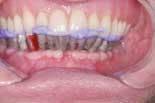

The fixed provisional restoration is placed in the mouth and screwed in place. The vertical dimension is confirmed and the occlusion adjusted. The screw holes are sealed with low viscosity polyvinyl impression material (figures 17 and 18).

When the final restorations are received from the lab, they are inspected on the mounted models (figures 26 and 27). The final restoration is placed in the mouth and screwed in place. The access holes are filled with Clip, pink opaque composite and tooth-colored composite (figures 28 and 29). Final occlusal adjustments are made and esthetics confirmed (figure 30).